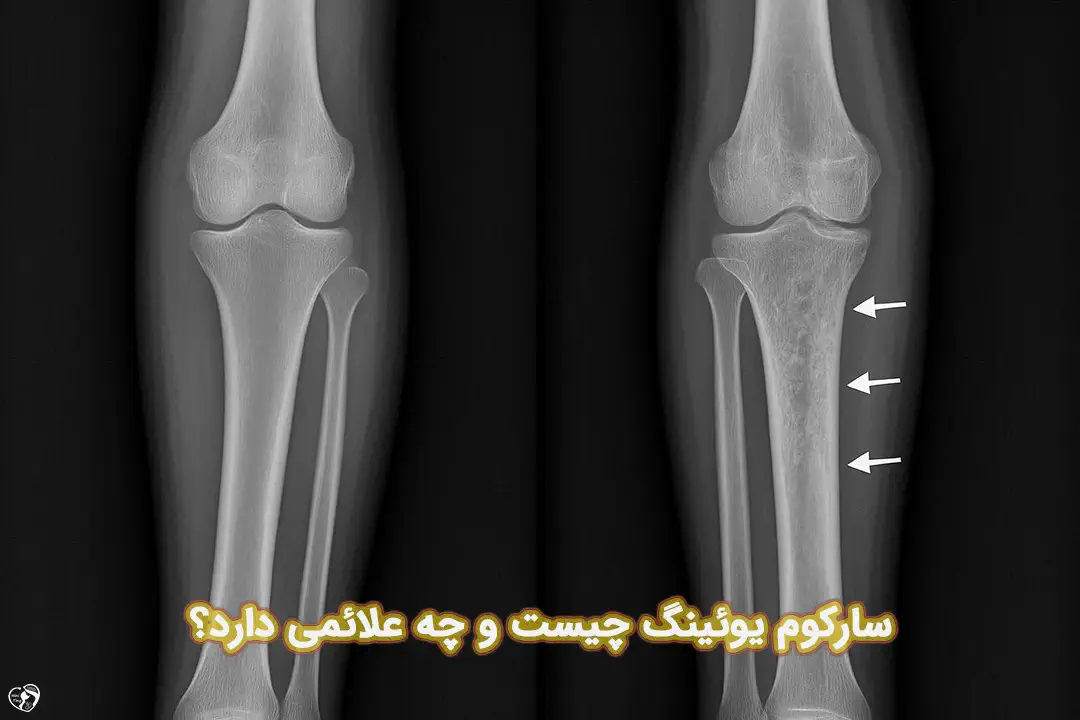

سارکوم یوئینگ یکی از سرطان های نادر استخوان و بافت نرم است که بیشتر در کودکان و نوجوانان دیده می شود. این بیماری می تواند به صورت درد، تورم یا توده ای در اطراف استخوان ها خود را نشان دهد و اگر به موقع تشخیص داده نشود، به دیگر اندام ها گسترش یابد. در این مقاله، به طور کامل درباره علت سارکوم یوئینگ، علائم، روش های تشخیص و درمان آن صحبت می کنیم تا والدین بتوانند آگاهانه مسیر درمان فرزندشان را دنبال کنند.

سارکوم یوئینگ (Ewing Sarcoma) نوعی تومور نادر و بدخیم است که معمولا در استخوان ها یا بافت های نرم بدن مانند ماهیچه ها، تاندون ها و رباط ها ایجاد می شود. این بیماری بیشتر در کودکان، نوجوانان و جوانان بین 10 تا 20 سال دیده می شود و در دوران بلوغ، زمانی که رشد استخوان ها سریع تر است، احتمال بروز آن بیشتر می شود.

در بسیاری از موارد، سارکوم یوئینگ در استخوان های بزرگ مانند ران، ساق پا، لگن یا تیغه شانه آغاز می شود، اما می تواند در هر استخوان یا حتی در بافت های نرم بدن نیز ظاهر شود.

علائم سارکوم یوئینگ ممکن است در ابتدا خفیف و مبهم باشند و به همین دلیل، گاهی با دردهای معمول رشد یا آسیب های ورزشی اشتباه گرفته می شوند. اما شناخت به موقع علائم بسیار مهم است. شایع ترین نشانه ها شامل موارد زیر هستند:

- درد استخوانی که معمولا متناوب است و شب ها شدت بیشتری پیدا می کند.

- تورم یا حساسیت در اطراف استخوان یا بافت های نزدیک به محل تومور.

- توده یا برآمدگی گرم و نرم زیر پوست که قابل لمس است.